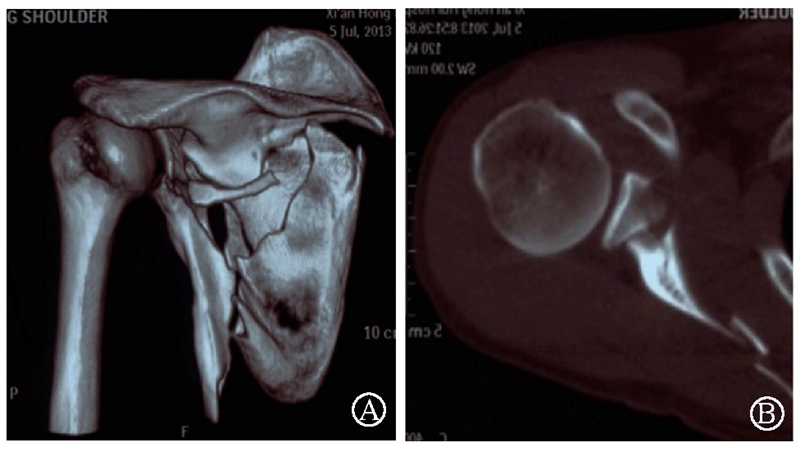

病例2为1例累及肩胛盂、肩胛颈和肩胛骨体部的复杂肩胛骨骨折(图11-12)。

术前设计采用跨骨折区域钢板螺钉固定(图13)。术中可见纵向骨折区域骨质薄弱,骨折粉碎严重,钢板放置位置有限,操作极其困难(图14)。术中采用多块接骨板跨骨折区域固定,术后X线片及三维CT重建显示复位满意(图15)。针对此病例,如果采用缝线辅助固定技术,可使手术操作过程简化,达到同样的固定效果(图16)。

图11 CT三维重建及轴位重建示肩胛骨骨折累及肩胛盂、肩胛颈和肩胛骨体部 图A:CT三维重建;图B:CT轴位重建